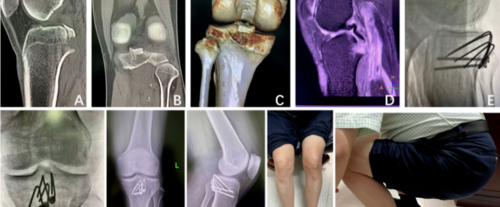

骨母细胞瘤是一种罕见的良性肿瘤,主要发生在轴骨中(图5A、5B、5C)。大约35%发生在长管状骨中,其中75%发生在骨干中。只有少数病例涉及骨骺。

图5A:19岁男性,骨母细胞瘤,有4个月的膝关节外侧疼痛病史。CT图像显示腓骨头部有膨胀性溶骨性病变(箭头所示)和少量的类骨基质。病变向胫骨后部突出。

图5B:19岁男性,骨母细胞瘤,有4个月的膝关节外侧疼痛病史。全身骨扫描图像显示腓骨头的孤立性病变和显著的放射性核素摄取。

图5C:19岁男性,骨母细胞瘤,有4个月的膝关节外侧疼痛病史。肿瘤切除和骨移植后的前位X线片。